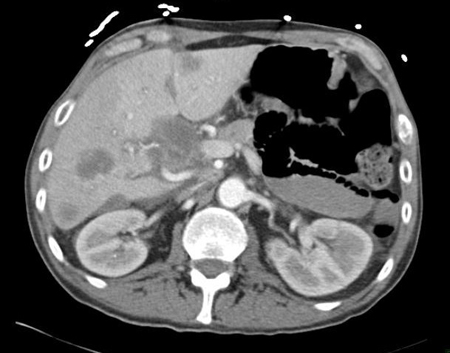

[Figure caption and citation for the preceding image starts]: CT abdomen with intravenous contrast, revealing numerous enhancing liver lesions in both hepatic lobes; percutaneous biopsy of a right lobe lesion revealed adenocarcinomaFrom the personal collection of Dr D. Cosgrove [Citation ends].